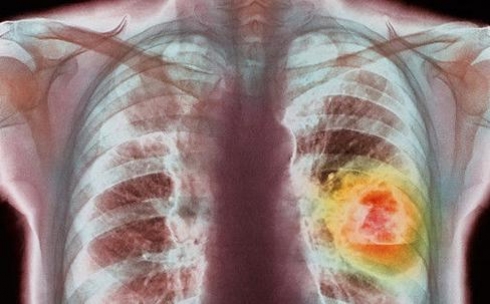

В Караганде врачи призывают людей не растить раковые опухоли годами

В Карагандинской области начался декадник, приуроченный ко Всемирному дню борьбы против рака. Декадник по профилактике и раннему выявлению онкологических заболеваний проводится с 1 по 10 февраля. В эти дни врачи-онкологи с удвоенной силой рассказывают людям об опасности данных заболеваний и надеются быть услышанными.

В 2015 году в Карагандинской области было выявлено 3200 онкологических больных, в 2016 году эта цифра выросла до 3500 человек. Из этого числа ¼ часть не подлежит лечению. К счастью, в числе областей, которые лидируют по показателям заболеваемости злокачественными новообразованиями, Карагандинской области нет.

В Управлении здравоохранения говорят, что в год на человека, который проходит химиотерапию, затрачивается около 20 миллионов тенге. Врачи призывают относиться ответственно к своему здоровью, проходить ежегодные обследования в кабинете первичного медицинского осмотра, где специалист уже при визуальном осмотре может обнаружить заболевание, а также проходить скрининговые обследования.

- Многие пациенты, обратившиеся со злокачественным новообразованием, зачастую говорят, что уплотнение обнаружили много лет назад, но обратились к врачу только сегодня. Конечно, это сокращает шансы на выздоровление, - говорит пресс-секретарь Управления здравоохранения Карагандинской области Айжан Иса.

В ведомстве говорят, что пройти скрининговое обследование могут люди не только определённых возрастов, но и все желающие. Достаточно изъявить желание в кабинете первичной медицинской помощи и попросить дать направление для прохождения необходимых обследований.